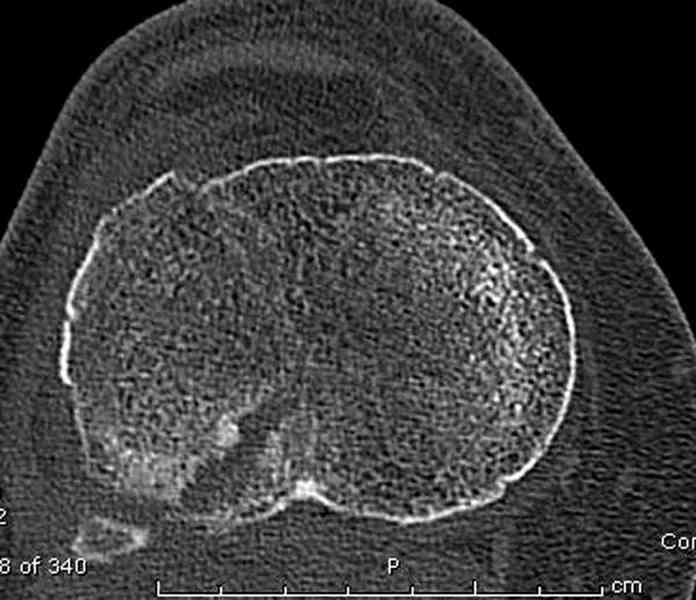

Вложение не в текстовом формате было извлечено…

Имя     : 3 lat tib plateau CT2.jpg

Тип     : image/jpeg

Размер  : 53226 байтов

Описание: отсутствует

Url     : http://weborto.net:8080/pipermail/ortho/attachments/20100926/dbcec959/attachment-0014.jpg

Для внутрисуставных переломов необходимо идеальное сопоставление, а

такая задача без КТ срезов усложнится. Только КТ надо делать после

дистракции сустава, иначе нельзя получить  объективную информацию.